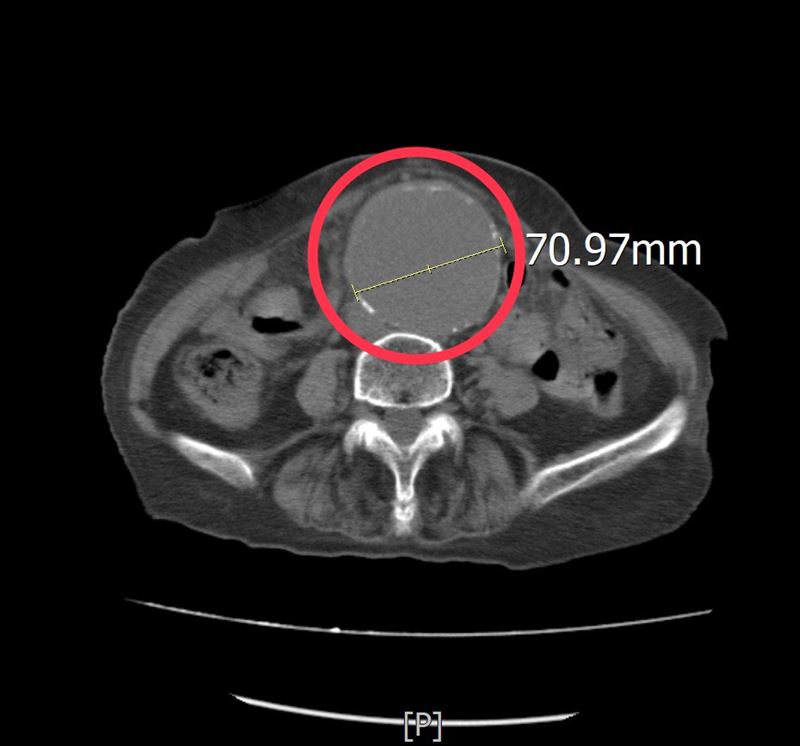

86歲阿嬤由家屬陪同到急診求診時,一再強調她左側下肢痠痛及腰部不適,沒有明顯外傷,但疼痛指數已達到8至10分。為了快速釐清病情,孫秀正醫師立即為病人進行床邊超音波檢查。透過即時影像檢查,發現患者的腹主動脈明顯擴張,直徑已超過7公分,高度懷疑為腹主動脈瘤,進一步安排電腦斷層檢查確認診斷,結果顯示確實為大型腹主動脈瘤。

孫秀正醫師表示,腹主動脈瘤,是腹部主動脈血管壁因退化或動脈硬化而逐漸擴張,當血管直徑持續增大,血管壁會變得脆弱,一旦發生破裂,可能在短時間內造成大量內出血,死亡率極高。當腹主動脈瘤直徑大於5至5.5公分時,破裂風險即明顯增加,而該患者的腹主動脈瘤已超過7公分,屬於極高風險狀態,因此必須爭取時間儘速處理。